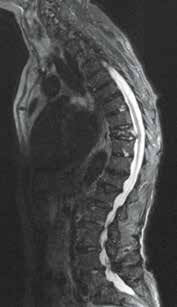

Es ist im Wesentlichen zwei Arbeitsgruppen zu verdanken, dass für bestimmte Aktivorthesen bzw. Aktivmieder Evidenz für ihren Einsatz bei Frauen mit postmenopausaler Osteoporose vorliegt (Abb. 2). So konnten Pfeifer et al. 32 in einer prospektiven randomisierten Crossover-Studie zeigen, dass das Tragen einer Orthese im Sinne einer Aktivorthese aus einer kalt verformbaren beweglichen und schwingenden Rückenpelotte mit einem Gurtsystem, welches einen individuell anpassbaren Formsitz erlaubt, über 6 Monate für täglich zwei Stunden zu einer Verbesserung verschiedener relevanter Parameter führt. So konnte im Vergleich zur Kontrollgruppe eine Verbesserung der Rumpfmuskelkraft, der Körperhaltung und der Lebensqualität bei über 60-jährigen Frauen mit Osteoporose und mindestens einer osteoporotischen Wirbelkörperfraktur nachgewiesen werden. Weiterhin wurden eine Abnahme des Kyphosewinkels und damit eine Verbesserung der Haltung und eine Schmerzreduktion im Vergleich nachgewiesen. Nach erfolgter Behandlung hielten diese Effekte für weitere 6 Monate an. Der Effekt wird erklärt mit einer Aktivierung der Muskulatur im Sinne eines Biofeedback-Mechanismus über die zugelastischen Materialien.